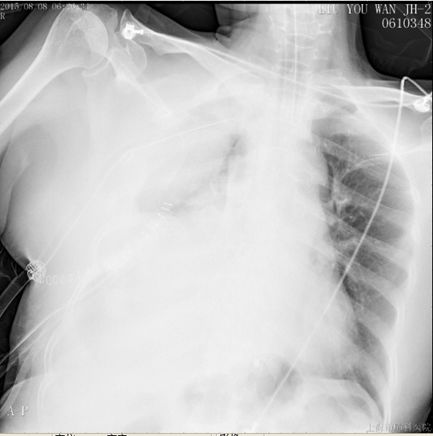

描述:溶栓2h后,胸引量:400ml

此时患者由中高危逐渐转为高危,则予以个体化剂量溶栓治疗:阿替普酶(爱通立)10mg 2min静推,20mg 2h静脉泵入。溶栓2小时后,患者血氧饱和度明显上升,生命体征趋于平稳。后续抗凝维持方案:克赛6000 IU 皮下注射 Q12H。